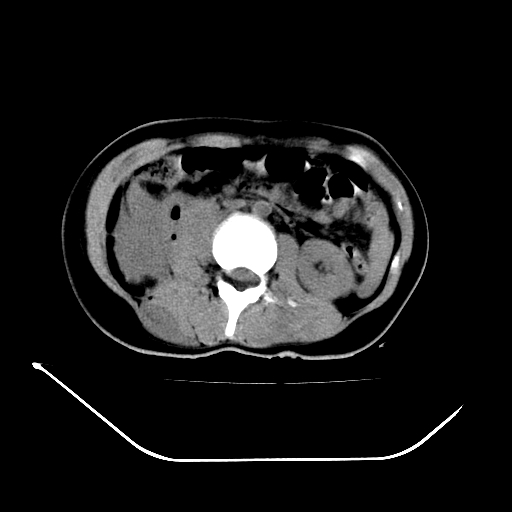

以下是引用liuyue在2008-7-19 13:02:00的发言:[br]1.肝右叶后下段及右肾挫裂伤伴腹腔积血。[br]2.右侧多发性肋骨骨折、横突骨折、右髂骨骨折伴周围软组织挫伤。[br]3.右侧腰大肌肿胀,并可见低密度影,如为气体,则肠道挫裂伤待除外。

以下是引用zhengfaming在2008-7-19 14:42:00的发言:[br]1.肝右叶后下段及右肾挫裂伤伴腹腔积血。脾脏挫裂伤待排[br]2.右侧多发性肋骨骨折、横突骨折、右髂骨骨折伴周围软组织挫伤。[br]3.右侧腰大肌肿胀,并可见低密度影,如为气体,则肠道挫裂伤待除外

以下是引用道哥在2008-7-19 16:52:00的发言:[br]肝右叶后下段及右肾挫裂伤、脾破裂伴腹腔积血。[br]2.双侧多发性肋骨骨折、横突骨折、右髂骨骨折伴周围软组织挫伤。[br]3.右侧腰大肌肿胀,并可见低密度影,如为气体,则肠道挫裂伤待除外。